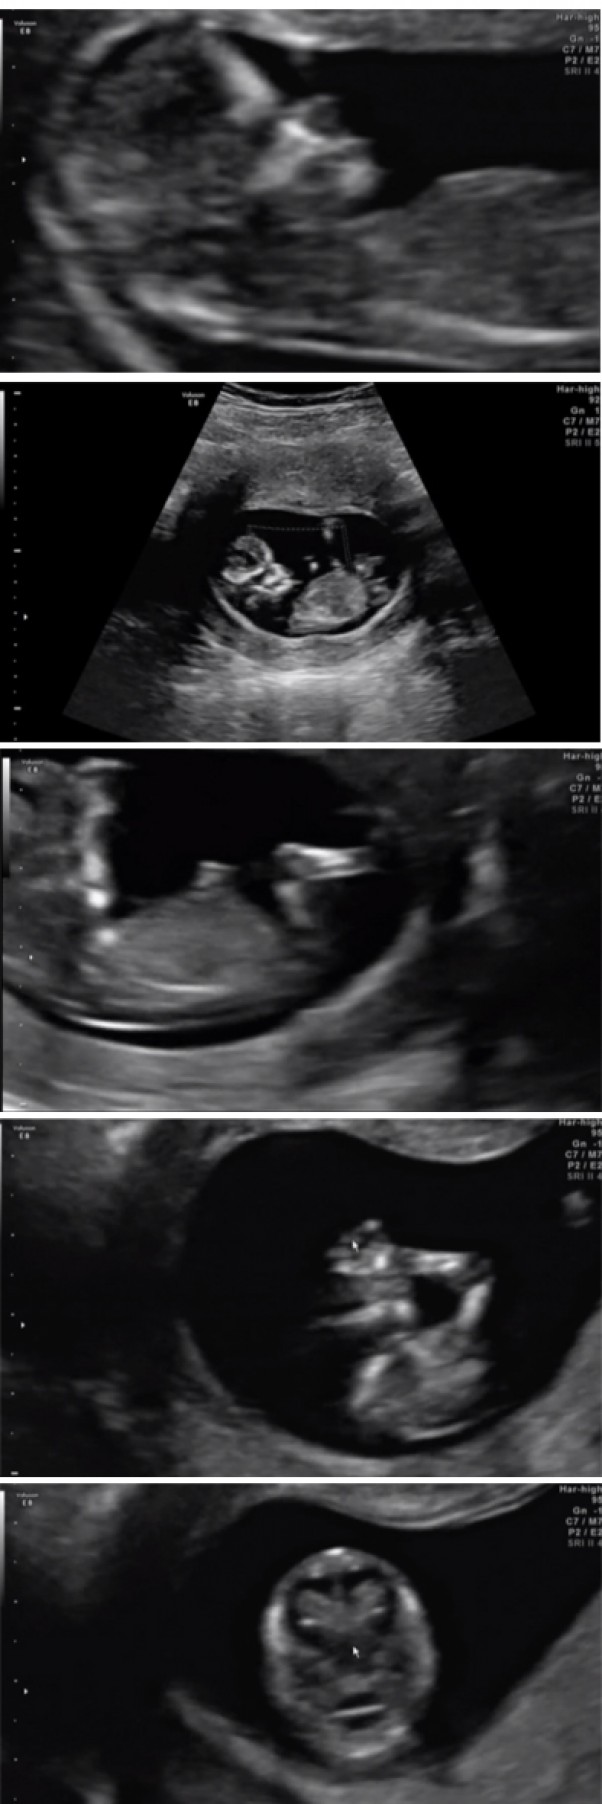

Wczoraj byliśmy z mężem na badaniach. Wyniki wszystkie super, a podpytując lekarkę o płeć, powiedziała "Ja bym stawiała na dziewczynkę". Hehehe, no to niebieskie ciuszki, nosidełka, torby itp. najprawdopodobniej nie były przeczuciem babci:P

Wspaniałe badanie, wspaniały widok, jakbym była bogatsza, kupiłabym taki sprzęt i codziennie oglądała moją dzidzię.